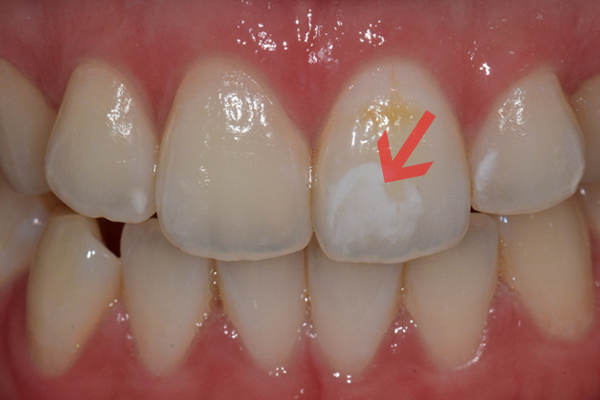

치아를 삭제하지 않고 레진을 치아에 침투시키는 원리로 치료합니다.

기존 재료를 사용함에 비해 치아 내부 투명도를 복원하기에 탁월하여 자연스러운 색과 질감으로 치아를 복원합니다.

치아 삭제가 필요하지 않는 것이 가장 큰 장점입니다.

치료 후